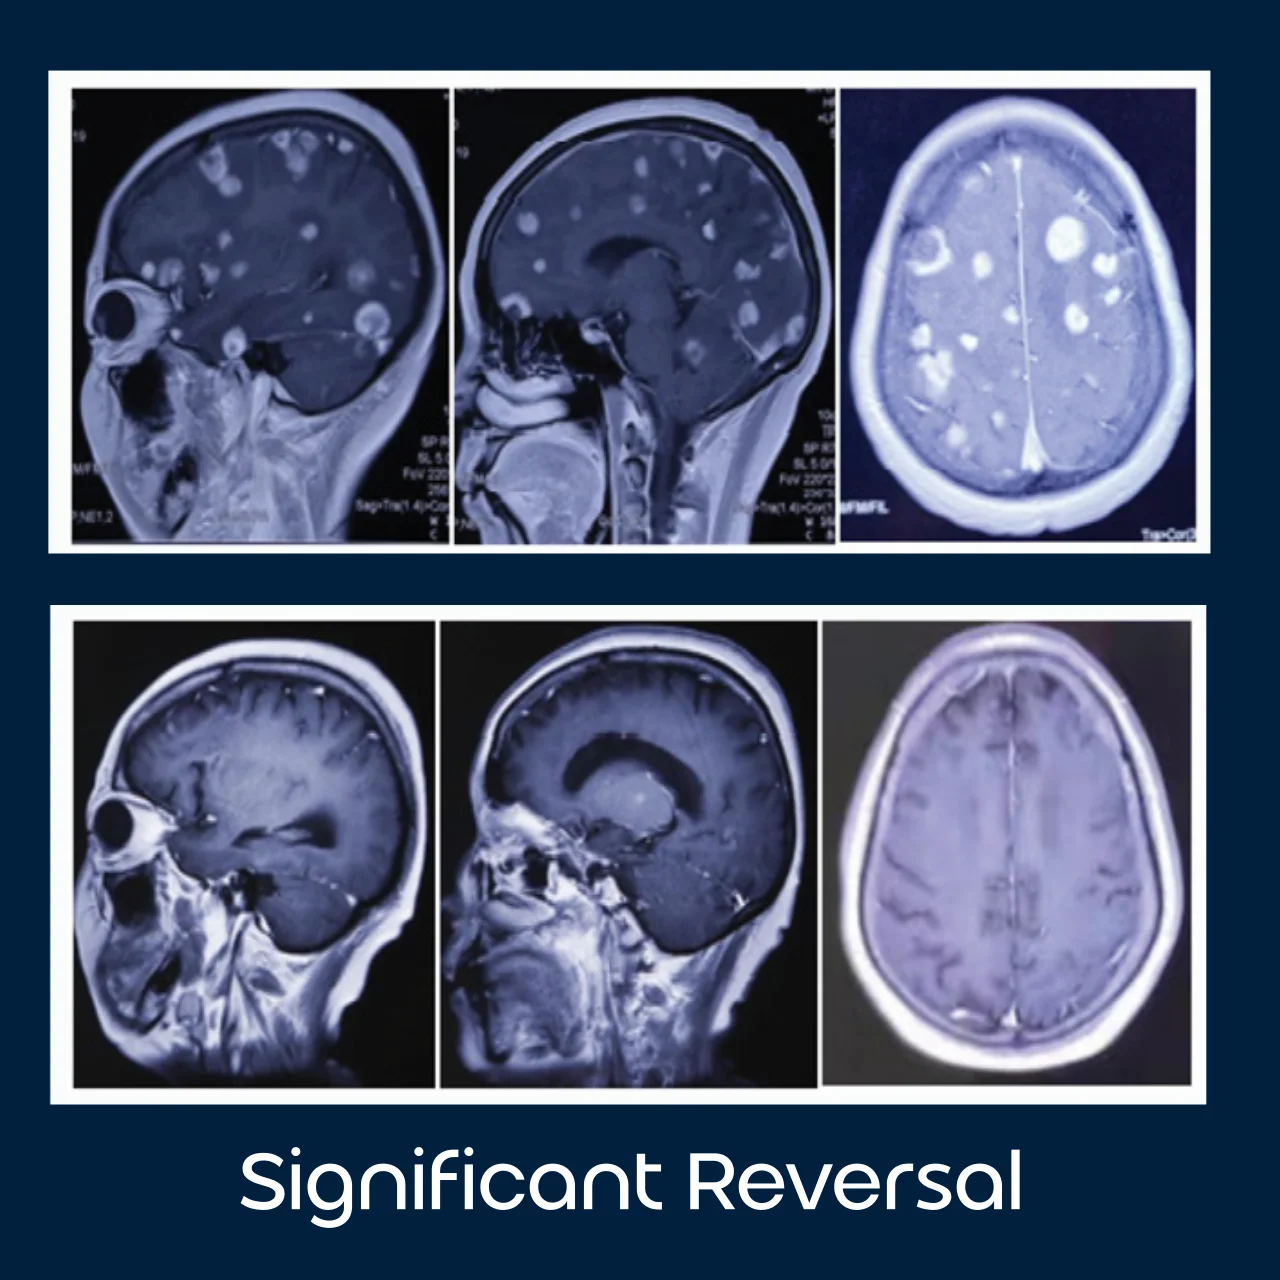

Molecular hydrogen is not a treatment for cancer; however, emerging research suggests it may play a supportive role in improving quality of life during conventional therapies.

Studies included in our Research section indicate hydrogen’s potential to reduce oxidative stress caused by treatments such as chemotherapy and radiation, while supporting cellular health and energy levels.

Its gentle, non-toxic nature makes it an area of growing interest in integrative and functional medicine settings as a complementary wellness strategy.

- Brain Metastases Completely Disappear in Non-Small Cell Lung Cancer Using Hydrogen Gas Inhalation: A Case Report